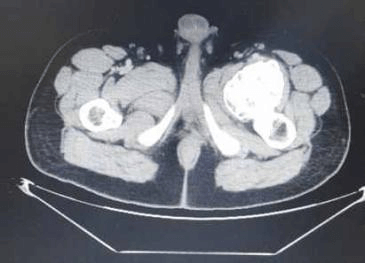

Here we report a 28 years old male present with pain in left hip and thigh due to proximal femoral Osteochondroma. Radiograph shows cauliflower-like mass originating from the left proximal femur. 3D CT scan of left thigh shows compression anterior displacement of femoral vessels near the bifurcation. This patient was treated with surgical en-bloc resection and histopathology was diagnostic of Osteochondroma.

Osteochondroma in the antero-medial aspect of subtrochanteric region of the left femur with origin abutting the lesser trochanter with a large cartilaginous cap causing compression anterior displacement of femoral vessels near the bifurcation.

3D CT Scan